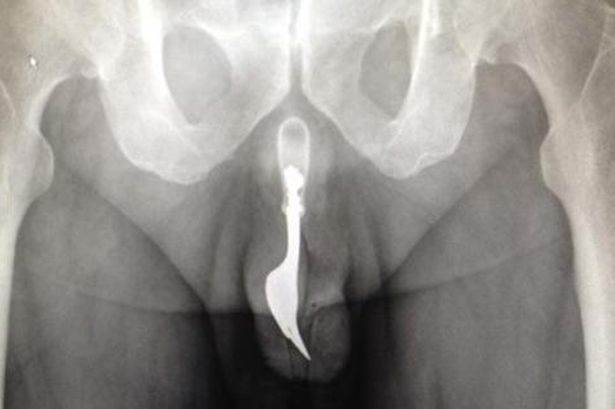

The Funny Images Thread